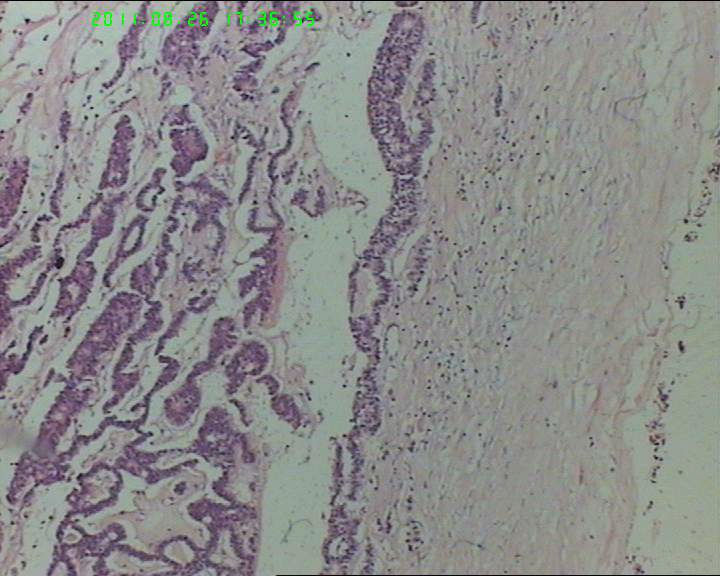

76岁女性卵巢巨大囊性肿物

卵巢肿物,大小18*14*10cm

,切面灰黄色,中央见一囊腔,12*4cm大小,未见内容物,内壁光滑。囊壁厚约4cm。

本例瘤细胞虽排列呈菊形团或腺管样,但瘤细胞核内未见核沟,核的形态也不是典型的石榴子样,故颗粒细胞瘤是个排除性诊断,本例还有一个特点是瘤细胞团周围有一收缩裂隙,提示其最有可能是类癌,唯一不足的是未见丰富的血窦